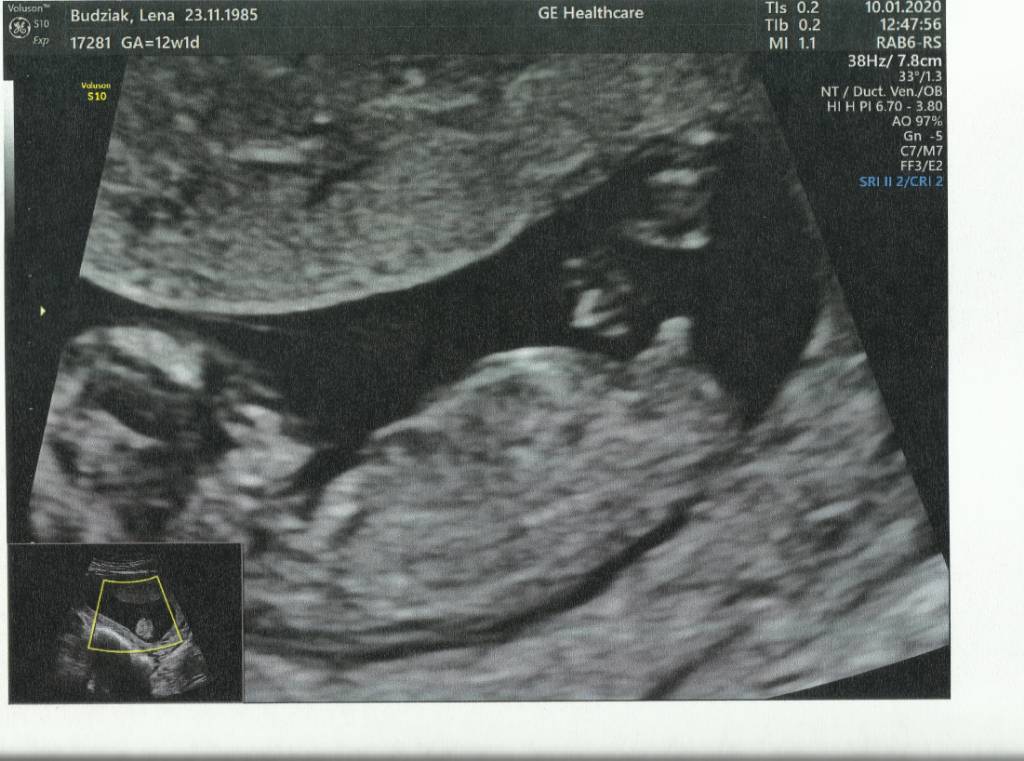

Jestem po usg prenatalnym okazało się że będzie jednak chłopak [emoji5] wszystko w porządku. Czekamy na wynik pappa .Zobacz załącznik 1067325

Ale dzidziula :) super którzy tydzień ?

12+3 Dzięki [emoji5]